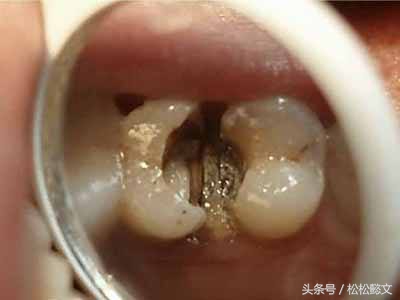

第三步:深龋

当您进食时,没法咬食物,您说:“还好,可以用另外一边牙齿咬。”

牙医告诫说:“病变已经破坏到了牙本质深层,牙齿有较深的龋洞,温度刺激,化学刺激以及食物进入龋洞时均引起疼痛,此时,及时做充填治疗的话还来得及保住牙髓。”

(深龋的龋蚀已达到牙本质深层,接近牙髓,或已影响牙髓。患者对冷、热、酸、甜都有痛感,特别对热敏感。这时多数需要作牙髓治疗以保存牙齿。)